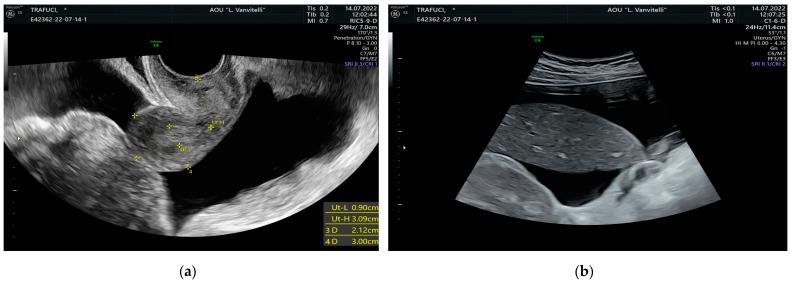

: Meigs syndrome is represented by a benign adnexal tumor, ascites, and hydrothorax. Even though the ovarian mass is often characterized by a fibroma-like origin, cancer antigen-125 (CA-125) serum levels could be elevated as in the development of ovarian cancer. Here, we present the case of a patient with Meigs syndrome and increased CA-125. : We performed systematic research for articles including similar cases in PubMed, EMBASE, and Scopus in February 2023, adopting the string of idioms: "Meigs syndrome AND Cancer antigen 125", and following the Preferred Reporting Items for Systematic Reviews and Meta-Analyses (PRISMA) statement. : Eligible records were 25. Hydrothorax was right-sided in 10 cases over 25; left-sided in two patients over 25. Concerning ascites, two patients showed more than 6 L of ascitic fluid, whereas three patients had 6 L or less. CA-125 elevation ranged from 149 IU/mL to 3803 IU/mL. Adnexal mass histotypes were: struma ovarii (12 cases), thecomas (two cases), fibrothecomas (five cases), fibromas (five cases), and one sclerosing stromal tumor (SST). : In postmenopausal women with elevated CA-125 serum levels and an adnexal mass suspicious for malignancy at ultrasound (US), ascites and pleural effusion, surgery, and histopathological examination are necessary. MS is a diagnostic option, with an excellent prognosis after exeresis of the mass.

梅格斯综合征的特征为良性附件肿瘤、腹水和胸腔积液。尽管卵巢肿块常表现为纤维瘤样起源,但癌抗原 125(CA-125)血清水平可能会升高,如同卵巢癌的发展过程一样。在此,我们报告了一例梅格斯综合征伴 CA-125 升高的患者。

符合条件的记录有 25 条。25 例中,10 例胸腔积液为右侧,2 例为左侧。关于腹水,2 例患者的腹水量超过 6 L,3 例患者的腹水量为 6 L 或更少。CA-125 升高范围为 149 IU/mL 至 3803 IU/mL。附件肿块组织学类型为:卵巢甲状腺肿(12 例)、卵泡膜细胞瘤(2 例)、纤维卵泡膜细胞瘤(5 例)、纤维瘤(5 例)和 1 例硬化性间质瘤(SST)。

对于绝经后妇女,若血清 CA-125 水平升高且超声(US)检查怀疑附件肿块恶性、腹水和胸腔积液,手术和组织病理学检查是必要的。MS 是一种诊断选择,切除肿块后预后良好。